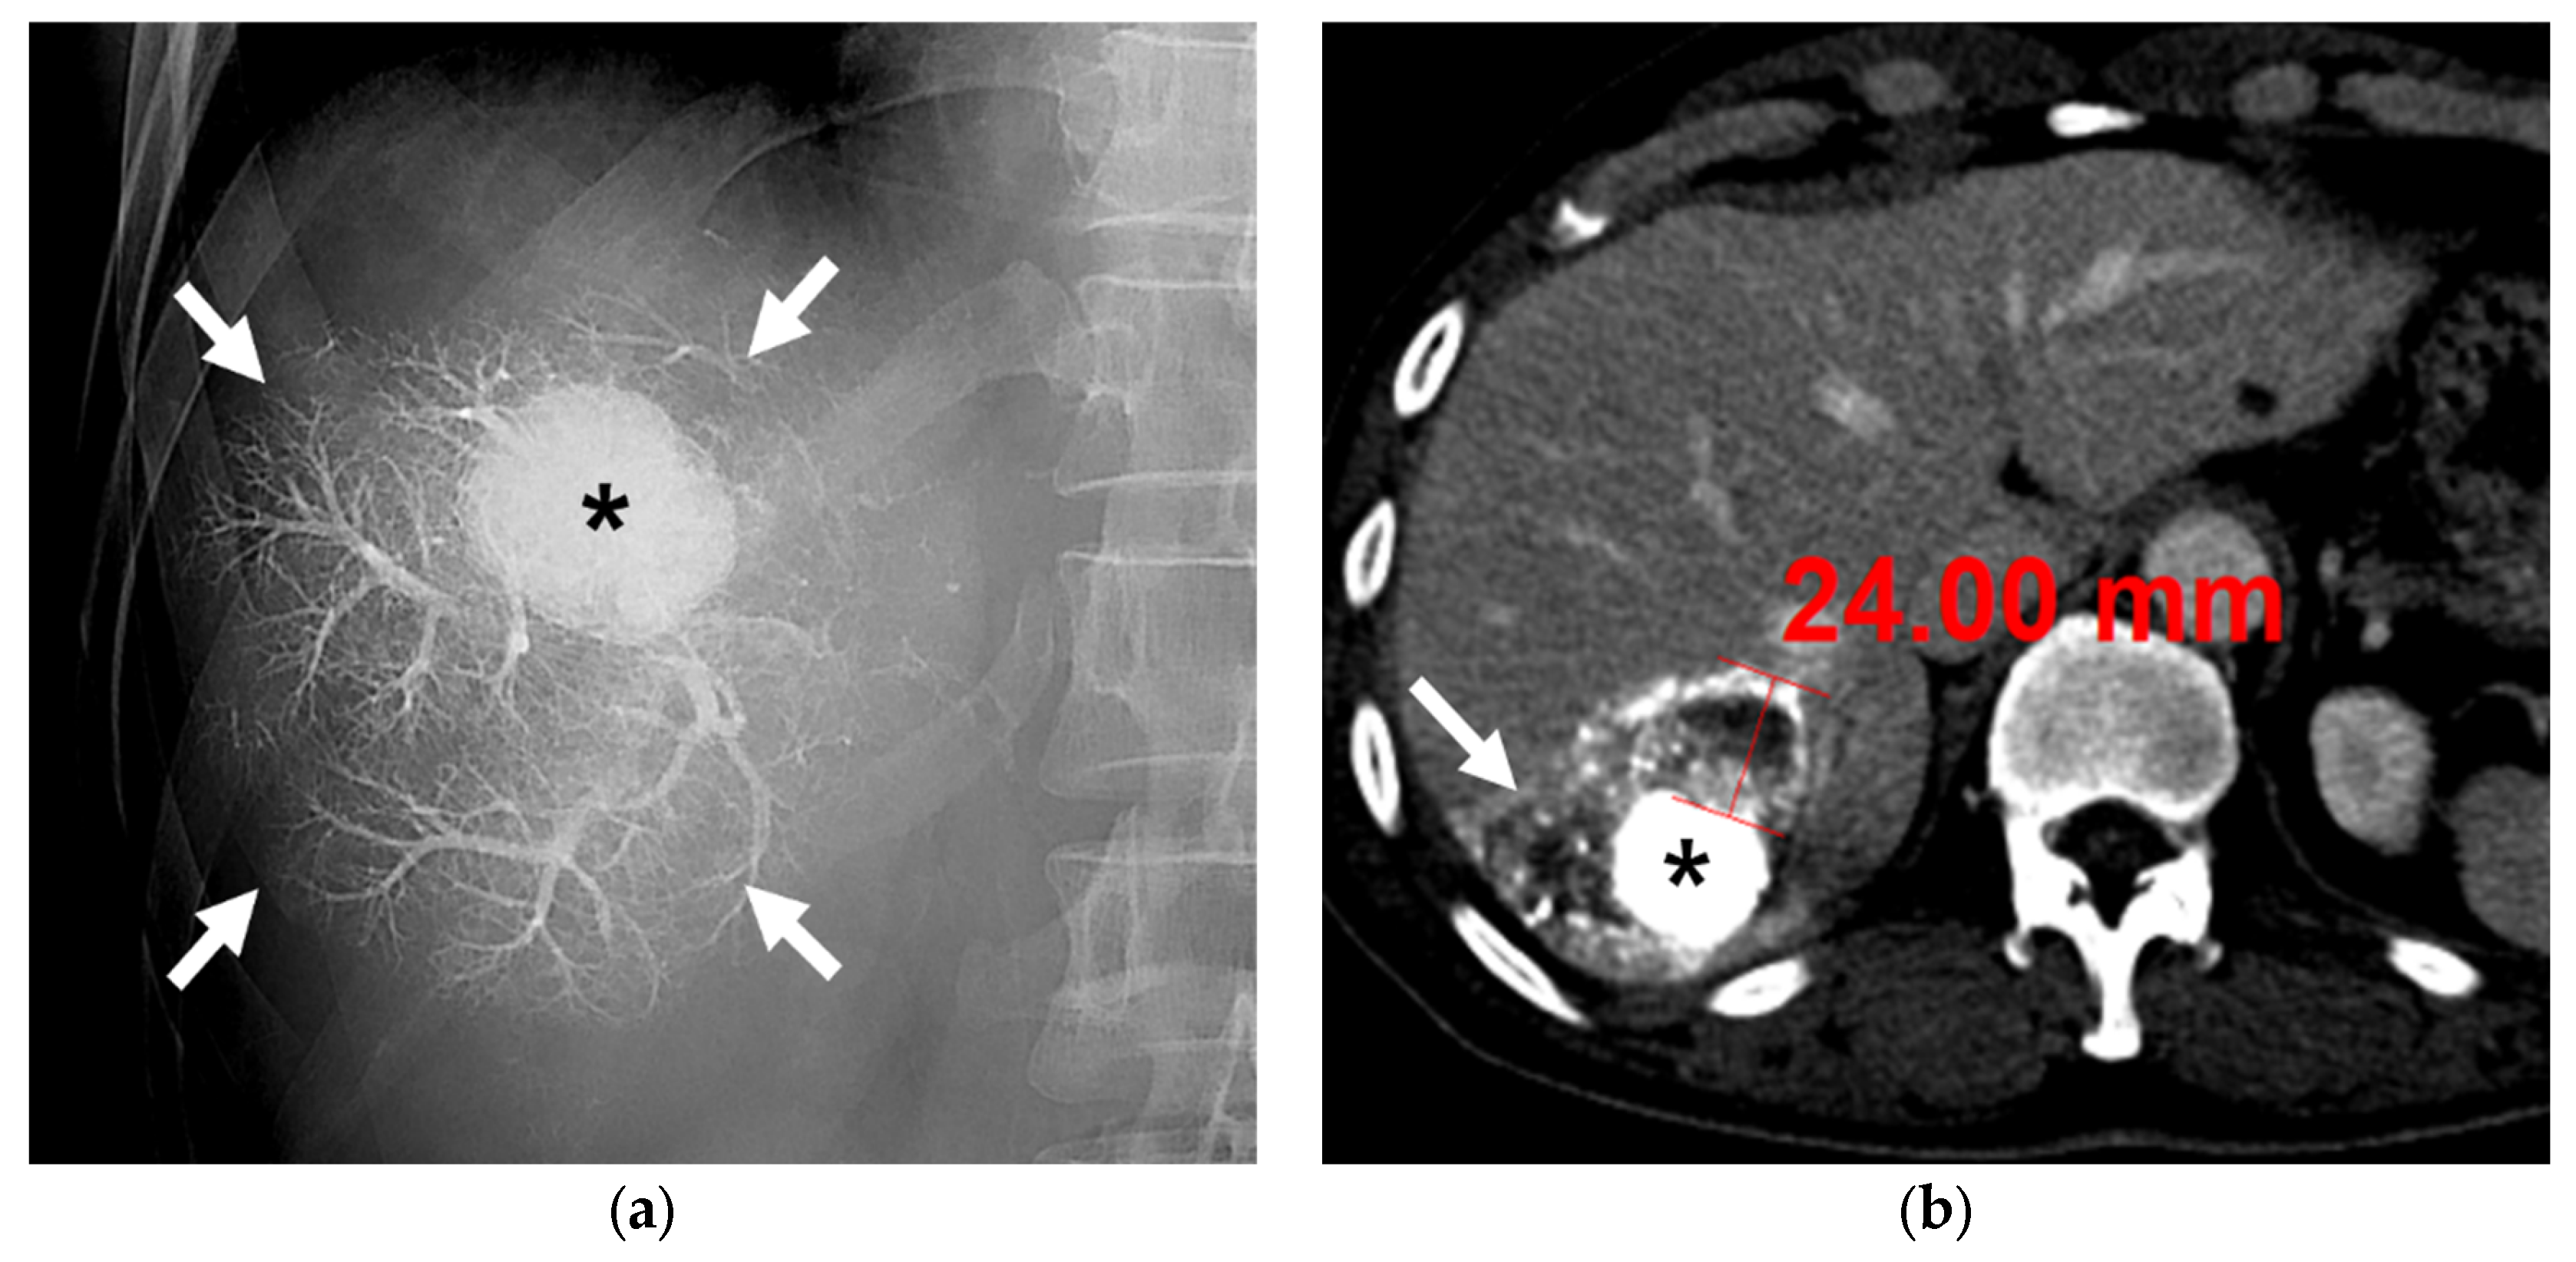

3.2. Radiological and Pathological Outcomes